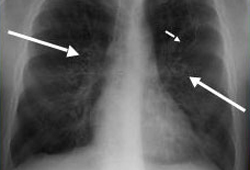

- chest x-ray

- high-resolution CT chest